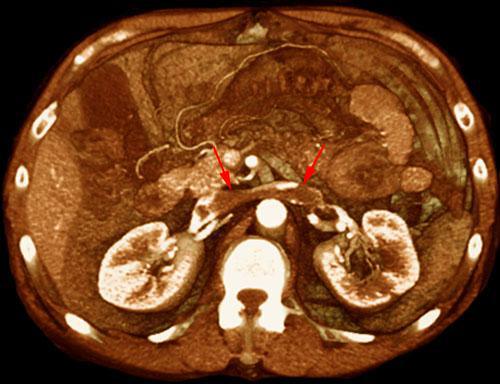

Trombosis de la vena renal izquierda

VR seccional. Visión axial caudal. TC contrastado en fase arterial mostrando un trombo ocupando la vena renal izquierda hasta la vena cava inferior (flechas)